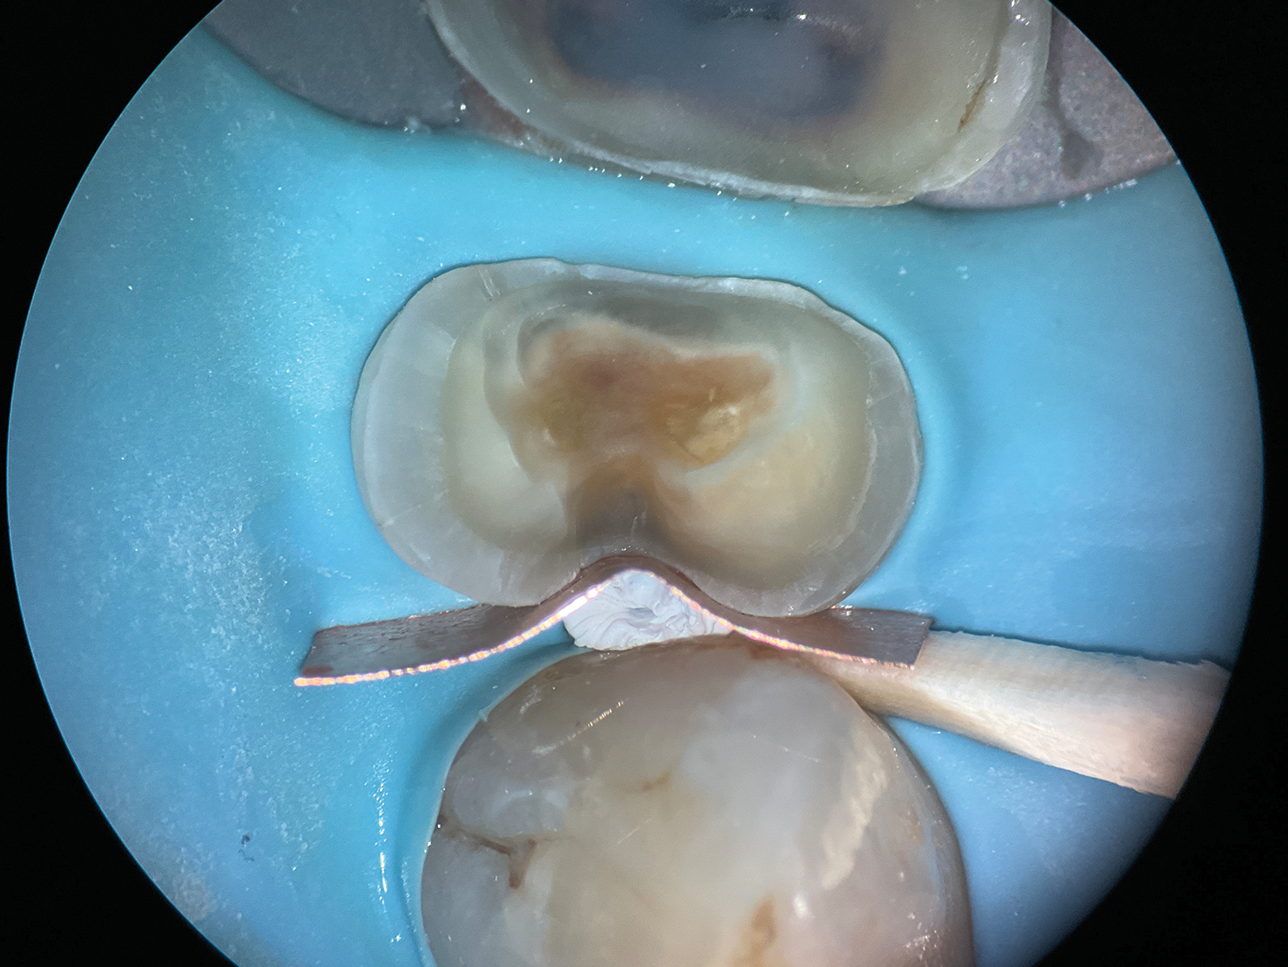

(9.) Close-up occlusal view of the maxillary first molar prepared for a matrix-in-matrix technique with a circumferential matrix supported by a 3-mil copper band inside for proper adaptation to the margin’s concave and convex areas. Note the addition of a liquid dam material placed between the two matrices for added stability.

Figure 9